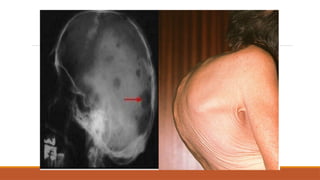

Multiple Myeloma

Increased clonal plasma cells in the bone marrow

Ix: The myeloma screen

X-ray

Myeloma: diagnosis

1. Production of a single monoclonal antibody (paraprotein)

◦ ‘M’ band in γglobulin region on serum/ urine electrophoresis

2.Increased clonal plasma cells in the bone marrow

◦ >20% monoclonal plasma cells on bone marrow biopsy

3. Evidence of organ damage (‘CRAB HAI’)